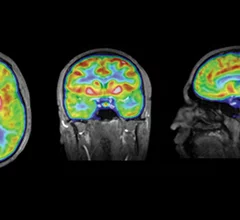

Physicians utilize medical imaging to see inside the body to diagnose and treat patients. This includes computed tomography (CT), magnetic resonance imaging (MRI), X-ray, ultrasound, fluoroscopy, angiography, and the nuclear imaging modalities of PET and SPECT.